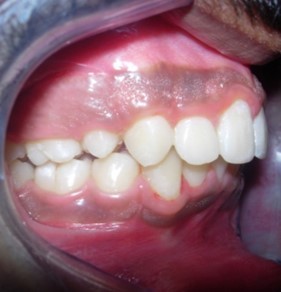

Results

The soft tissue frontal and profile improved dramatically. (Figure 7a-b). The bilateral posterior crossbite was corrected. The severe increase in overjet of about 13mm was effectively reduced to 3mm and the severe deep bite was also corrected (Figure 7c,Figure 7d). Fixed maxillary and mandibular lingual retainers were given. (Figure 7e, Figure 7f). Post orthodontic treatment, normal root inclinations of the teeth and normal alveolar bone levels was observed. (Figure 8).

Figure 7d.Post treatment intra-oral – Right